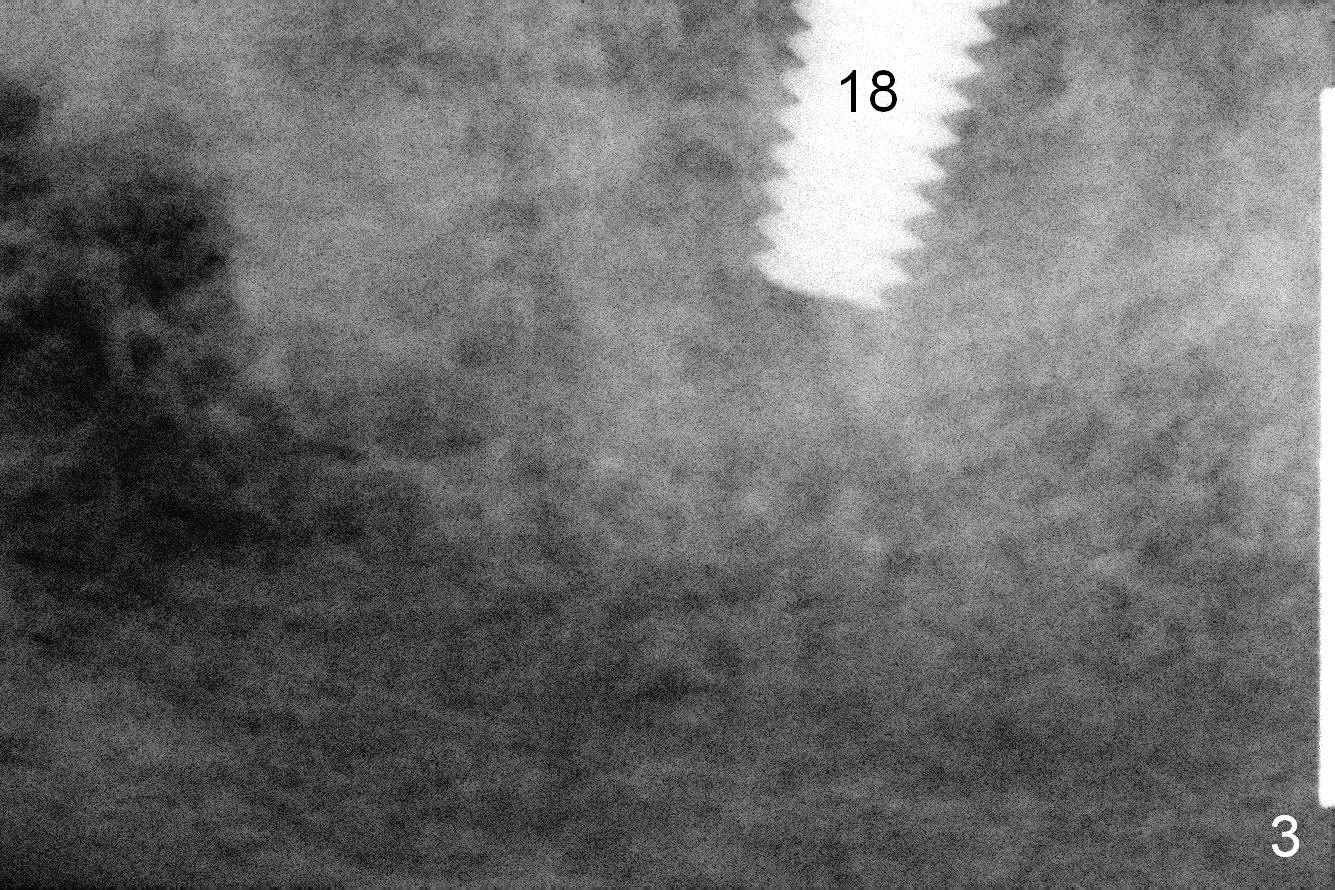

The sites of osteotomies at #18 and 20 are decided by the surgical stent (Fig.1). A 4x14 mm implant is placed at the site of #20 (Fig.2), and a 5x14 mm one at #18 (Fig.3) with primary stability. When 3 mm long abutments are placed for an immediate provisional (Fig.4 A), there is no or limited clearance with the opposing dentition (Fig.5). In spite of the fact that the implants are placed deeper, the abutments and the opposing supraerupted teeth #13 and 15 (Fig.5 arrows) have to be reduced. Finally the abutment at #18 has to be removed. No provisional is fabricated. Periodontal dressing is applied around the abutment at #20 and the adjacent teeth. It appears that the tissue-level implant is not suitable for the 2nd molar with limited vertical clearance.